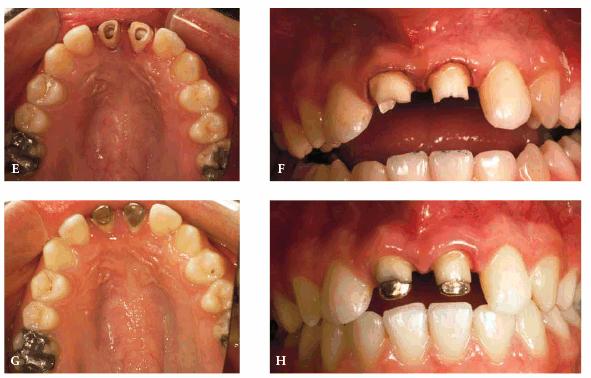

TREATMENT: Because saving teeth was a step-by-step procedure involving

endodontic treatment, periodontal surgery, and reconstructive techniques, the

treatment plan could be changed if one of the suggested treatments failed.

Endodontic therapy had already been completed on both central incisors. These

surgical procedures were performed next: removal of the tooth fragments that

were fractured vertically, labial and lingual gingivectomy and gingivoplasty,

palatal ostectomy, and labial frenectomy (Figur 323s1823d e 18-7C). Approximately 5 mm of palatal

plate was removed to expose new margins on the fractured teeth (Figur 323s1823d e 18-7D). After the tissue healed, gold

posts were constructed and cemented on the two maxillary incisors (Figur 323s1823d es 18-7E to

H). Final

preparations were made, and impressions for aluminous porcelain crowns were

made. The two crowns were seated (Figur 323s1823d es 18-7I

and J Figur 323s1823d e 18-7K is a radiograph of the teeth at the

end of treatment.

Figur 323s1823d e 18-7C and D: Following endodontic therapy and removal of the fractured tooth fragments, periodontal surgery to lengthen the exposed crowns was performed.

Figur 323s1823d e 18-7E to H: Next, two posts and cores were constructed for the endodontically treated teeth.